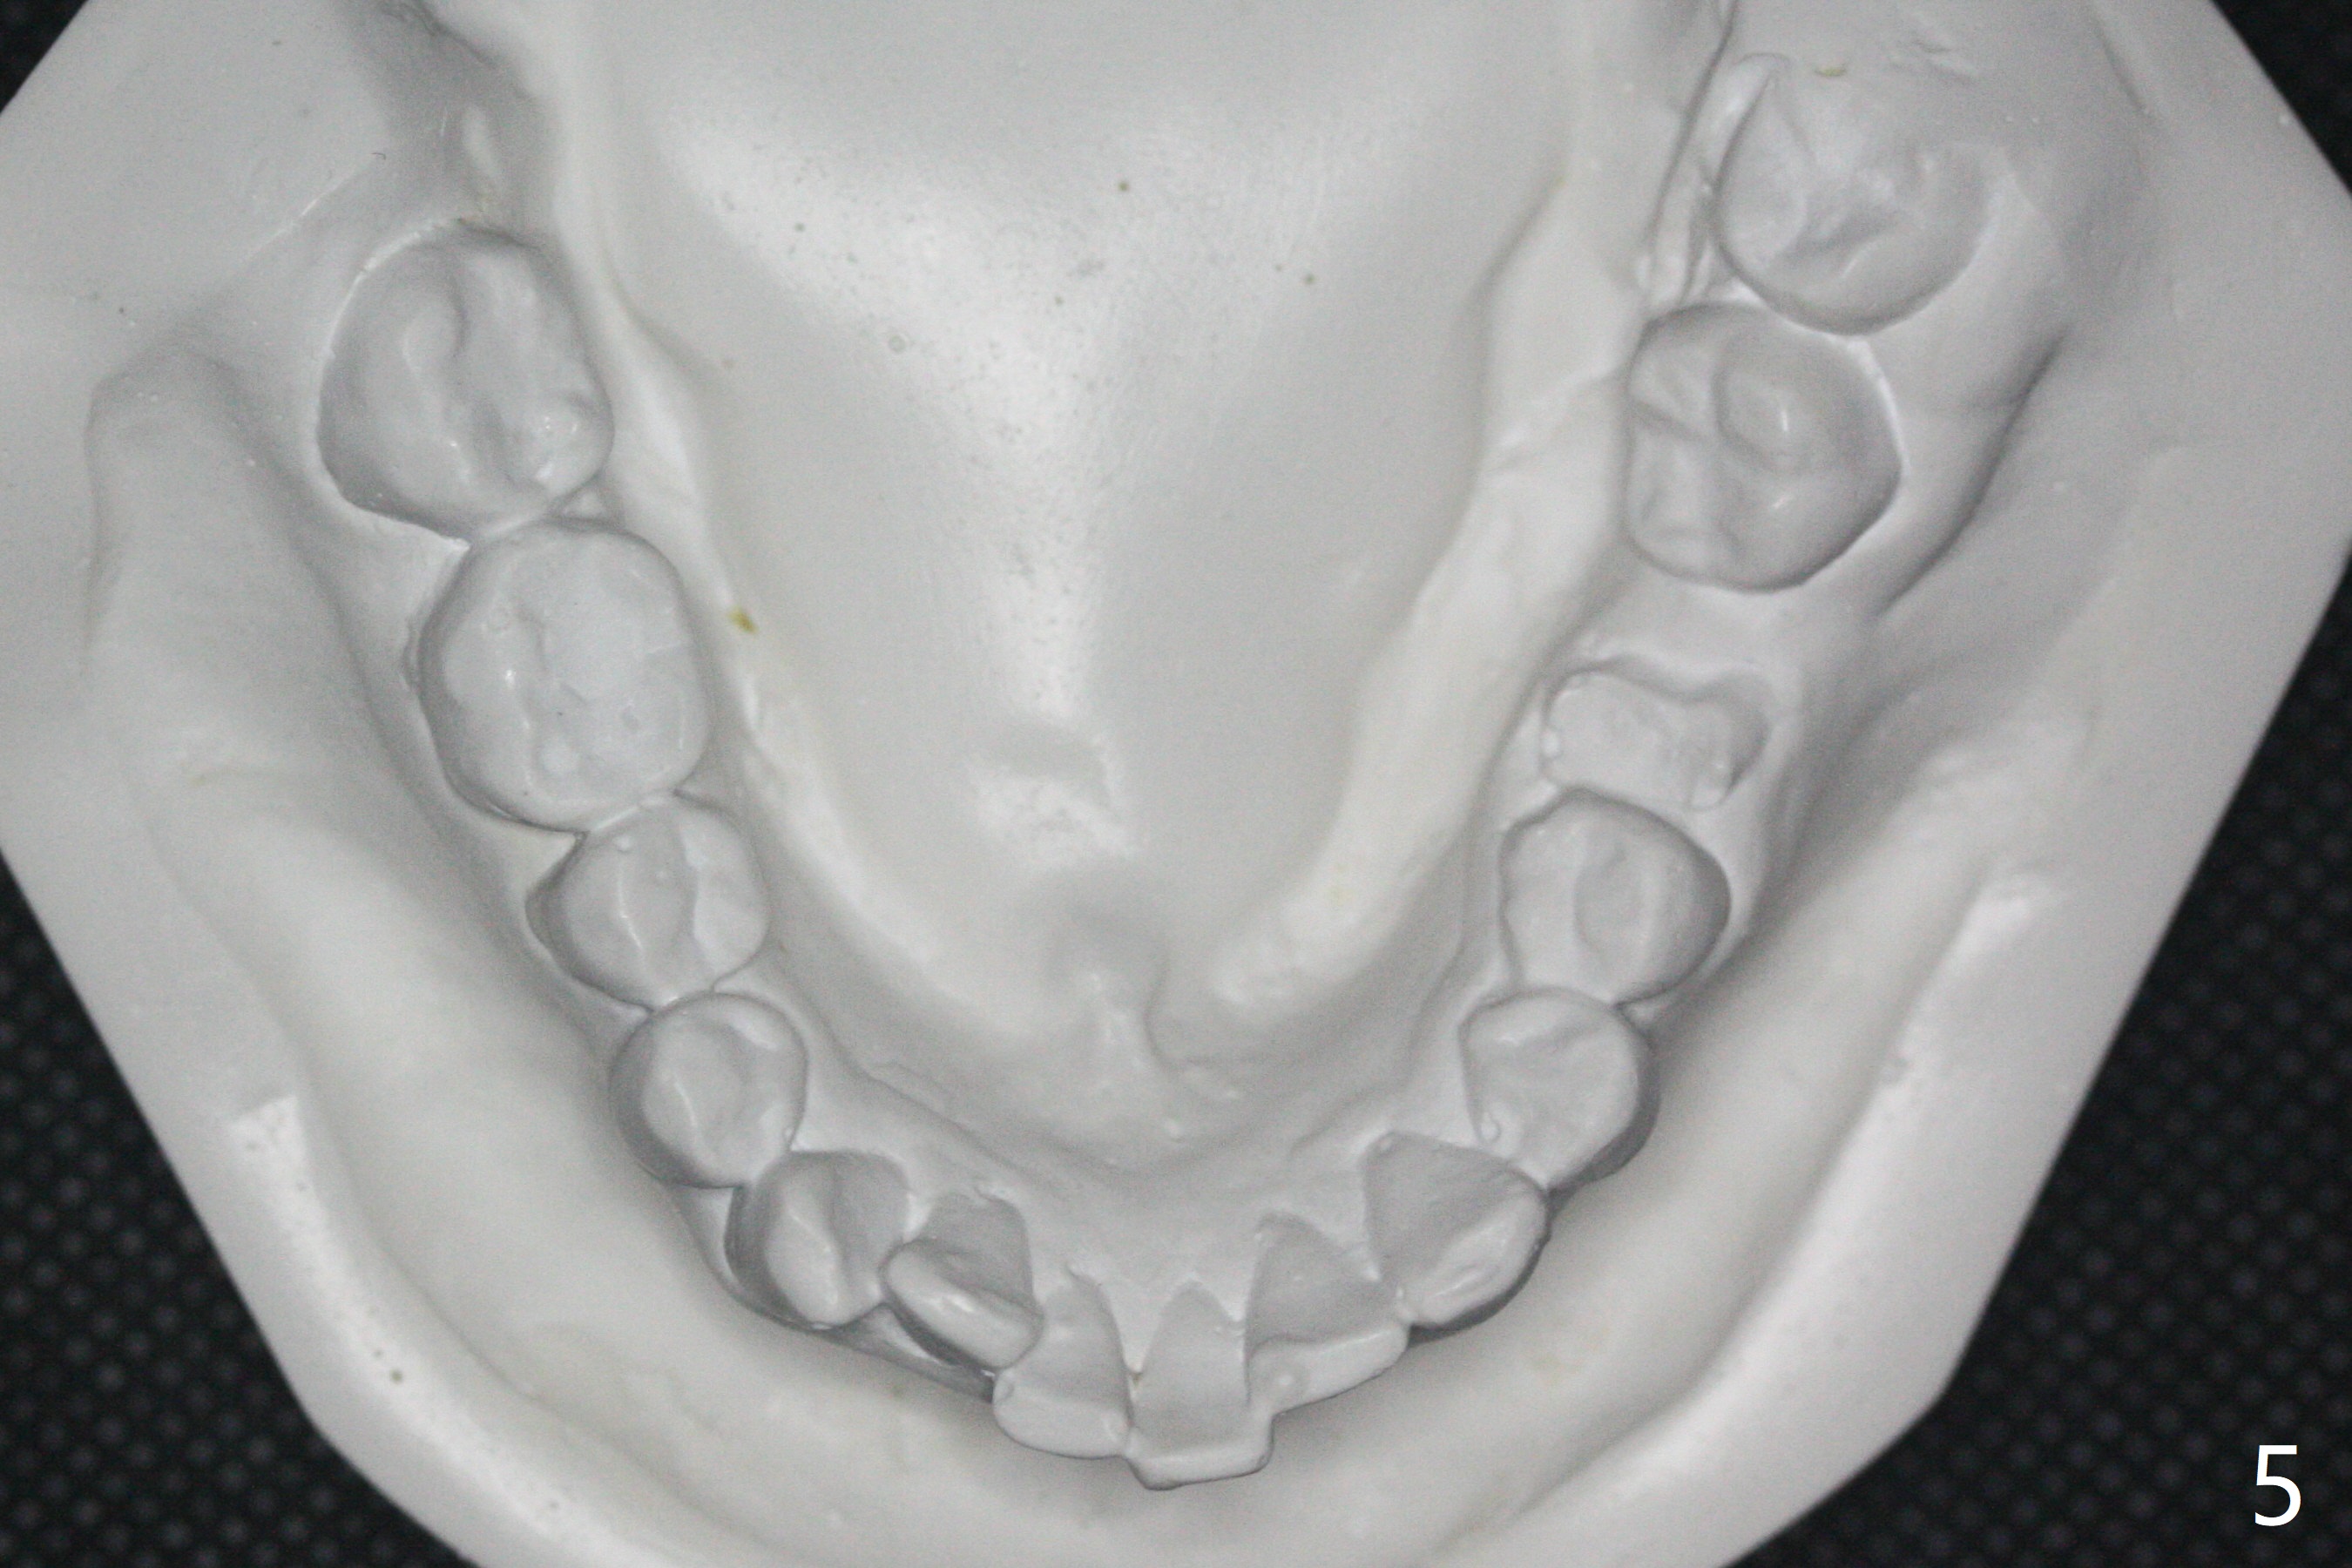

31岁女,牙周炎,安格氏二类错𬌗(图一至八),深洗后,同意牙齿矫正,但是要求保留左下智齿,前移7,8,取代6,左上6过度萌出(图三:箭头)。

初步计划:第一期安置矫正器,排列,建立正常前牙覆合覆盖,二类牵拉。尽量竖直左下7,8(图十一:白色轮廓);使用两个微型植体(图九:黑线(两个植体之间放置power chain(红线)))压入左上6(图十(圆圈:近中微型植体),与图三对比),为左下7近中移位(红色箭头)创造空间。

第二期在左下4和5之间植入微型植体作为支抗(图十一:红色),利用7远中长勾(粉红色)和橡皮筋,先让7平行近中移位,控制根torque。A 31-year-old woman with Class II Division I malocclusion requests orthodontic treatment without extraction of LL8. U8s and LL6 have been extracted with SRP. The 1st stage will be alignment , intrusion of UL6, upright of LL7 and 8 and correction of Class II malocclusion using double twin.